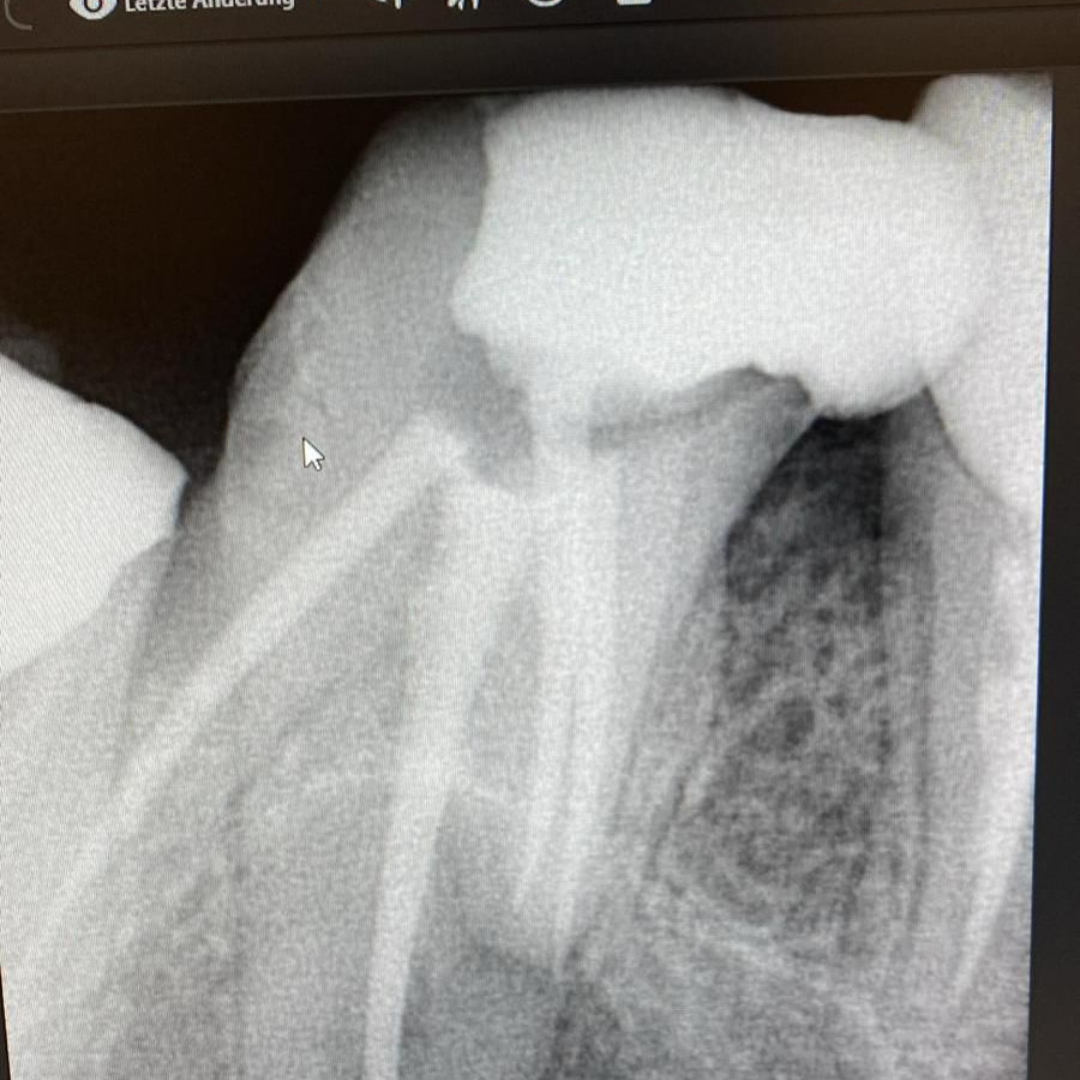

Throughout my studies, I immersed myself in learning, not just from books, but through hands-on experience at a local dental clinic. I spent countless hours there, treating patients and gaining invaluable practical skills. The joy and relief I saw in their eyes after each session were my greatest rewards. My humility and dedication earned me the love and respect of everyone around me.